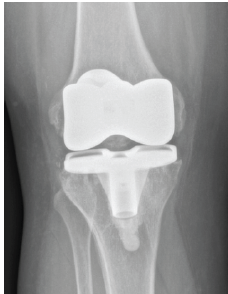

Extended Antibiotic Spacer use in an Infected Total Knee Arthroplasty with Mycobacterium intracellulare – A Case Report

Jayanth Kumar , Mason Fawcett , Musab Gulzar , Andres Lopez , Julie Shaner

………………………………p.14-18